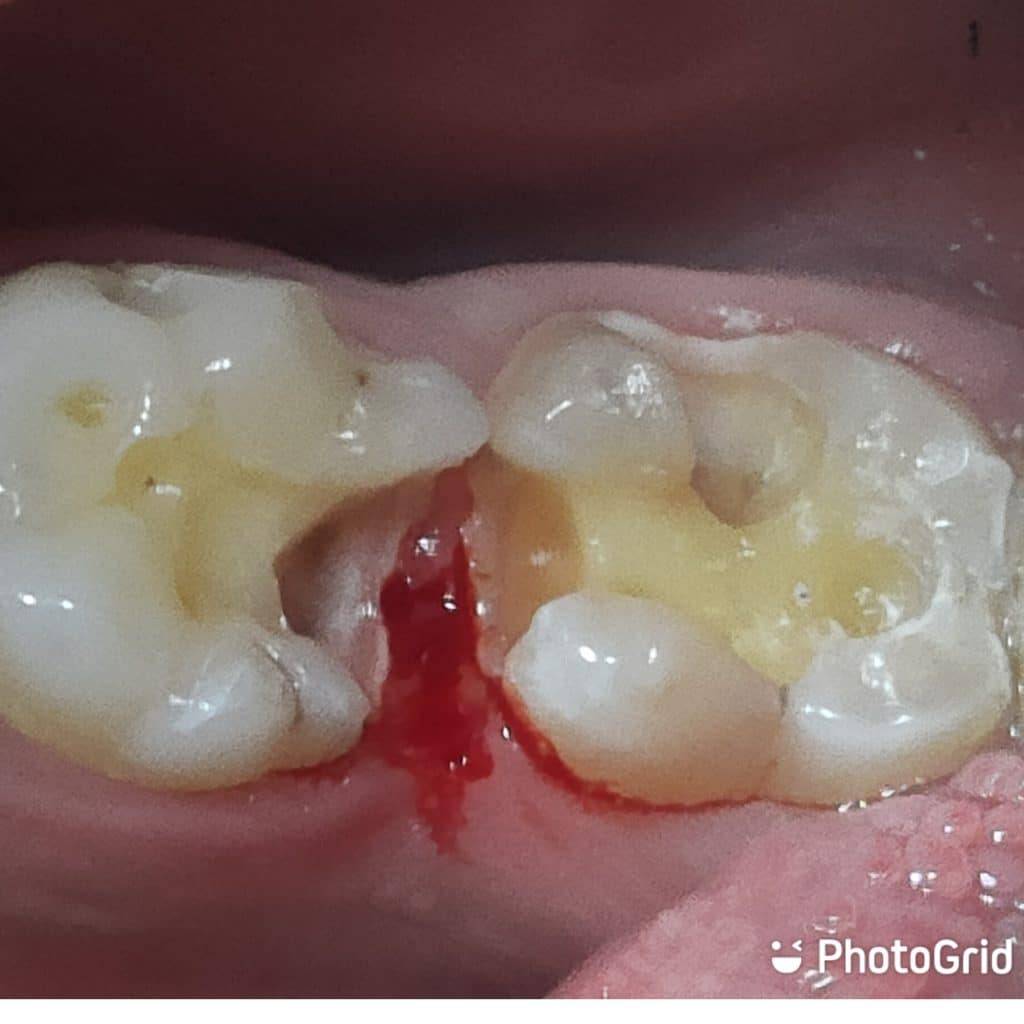

The following case came to dental office complaining from old destructed amalgam restoration.

After,proper diagnosis each tooth revealed healthy pulp condition .

1- I started removing old restoration with medium size diamond rose head also, removing all undermined enamel

2- cavity design was preformed properly in each tooth